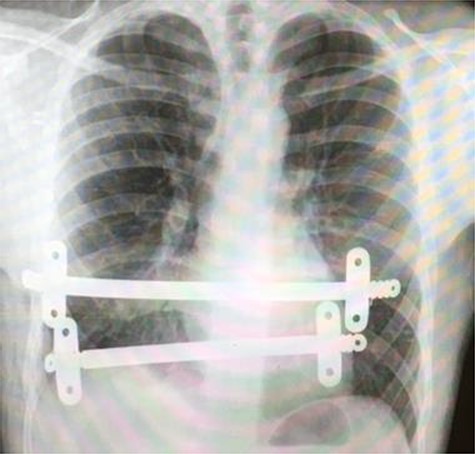

Superior intraoperative view of the laparotomy used to access and remove the second migrated bar.

Our patient was followed up annually. After two and half years, he developed a right-sided wound infection, initially treated with antibiotics. It was decided to remove the bar for prevention of recurrent infection. The chest X-ray showed migration of the lower-placed bar (Fig. 2). The upper bar and associated stabilizers were removed through the bilateral small incisions without any complication; however, the lower bar was not palpable. Therefore, a left-side thoracotomy was performed; however, the bar was not found in the chest. The incision was extended to a midline laparotomy (Fig. 3). This revealed an erosion of the bar in to the stomach after passing over the left lobe of the liver (Fig. 4). The bar and stabilizers were completely removed, and the hole in the stomach was closed directly with sutures. The patient was discharged home without any further complication after successful recovery.